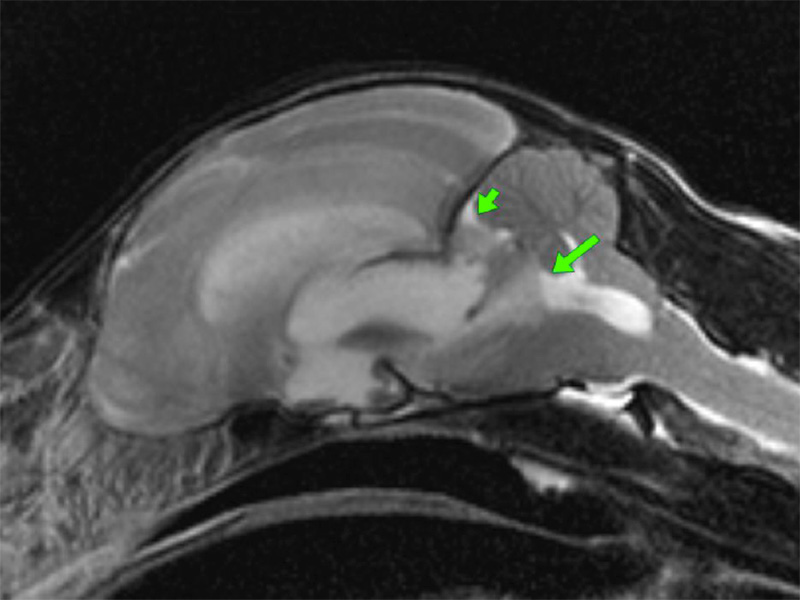

- Imaging: Imaging the feline brain, ears and nasal cavity (TBC)